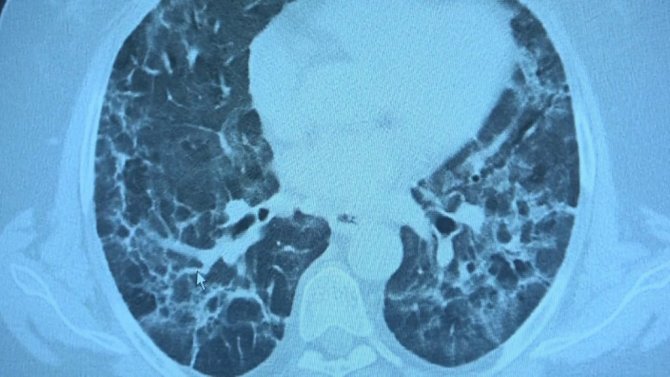

Korona virüs hastalığını atlatmış kişiler belli bir zaman geçtikten sonra halsizlik, nefes darlığı, enerjisi bitmiş şekilde tekrar kliniklere başvuru yapıyor. Uzmanların "uzamış Covid" ve "post Covid" dedikleri bu durum hem hastaların hem de hasta yakınlarının yaşam kalitesini olumsuz etkiliyor. Bu kapsamda 10 binin üzerinde Covid-19 hastası tedavi eden VM Medical Park Samsun Hastanesi'nde görevli Göğüs Hastalıkları Uzm. Prof. Dr. Şevket Özkaya ve Dr. Yağmur Sarıtaş klinikte karşılaştıkları yeni bir durumla ilgili bilgi verdi. Prof. Dr. Şevket Özkaya, Covid-19 geçirmiş ve tekrar farklı şikayetlerle kendisine başvuru yapmış hastaların akciğerlerini inceledi. Hastaların akciğerlerinde sekel lezyon denilen lekelerin görülmeye devam ettiğini belirtti.

Kliniğe gelen kişilerin akciğer tomografilerine inceleyen Prof. Dr. Özkaya, "62 yaşında bir teyzemiz 11 Mart'ta yoğun bakımda solunum yetmezliği ile hastaneye yattığında hayati tehlikesi vardı ve Covid- 19'u atlattı. Yalnız aradan 3 ay geçmesine rağmen hala akciğerinde Covid - 19'un uzamış etkileri dediğimiz sekel lezyonları var. Bu hasta nefes darlığı çekiyor. Diğer bir vaka örneği verirsek, 62 yaşında bir erkek hasta. Mart'ın sonlarında geldiğinde röntgeninde küçücük buzlu camları vardı. Birden Nisan'ın ilk haftası 10 gün içinde çok yaygın lezyonlar olmaya başladı. Yoğun bakımda takip etmek zorunda kaldık. Bu hastamızın hayatı kurtulduktan sonra filmine baktığımızda yine sekel lezyonlar görüyoruz. Böyle yıpratıcı, harap edici bir klinik tablo ortaya çıkıyor" diye konuştu.